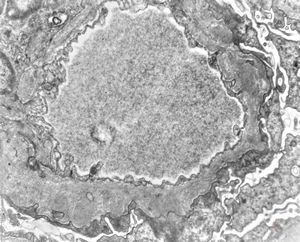

M,67y. | normal kidney

F,49y. | normal kidney

M,34y. | normal kidney

F,2y. | normal kidney